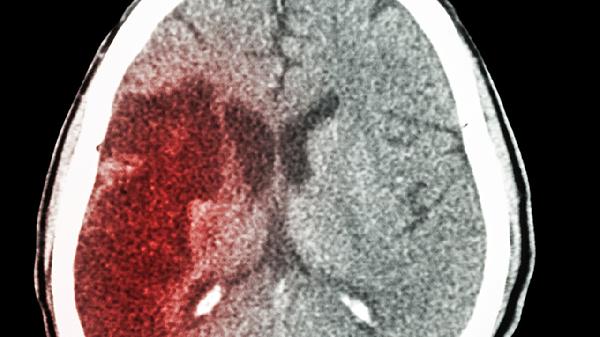

65岁后,脑梗进入高发期,建议:平时做好3件事,关键时刻能救.命

二、预警信号的识别指南

三、急救时差争夺战